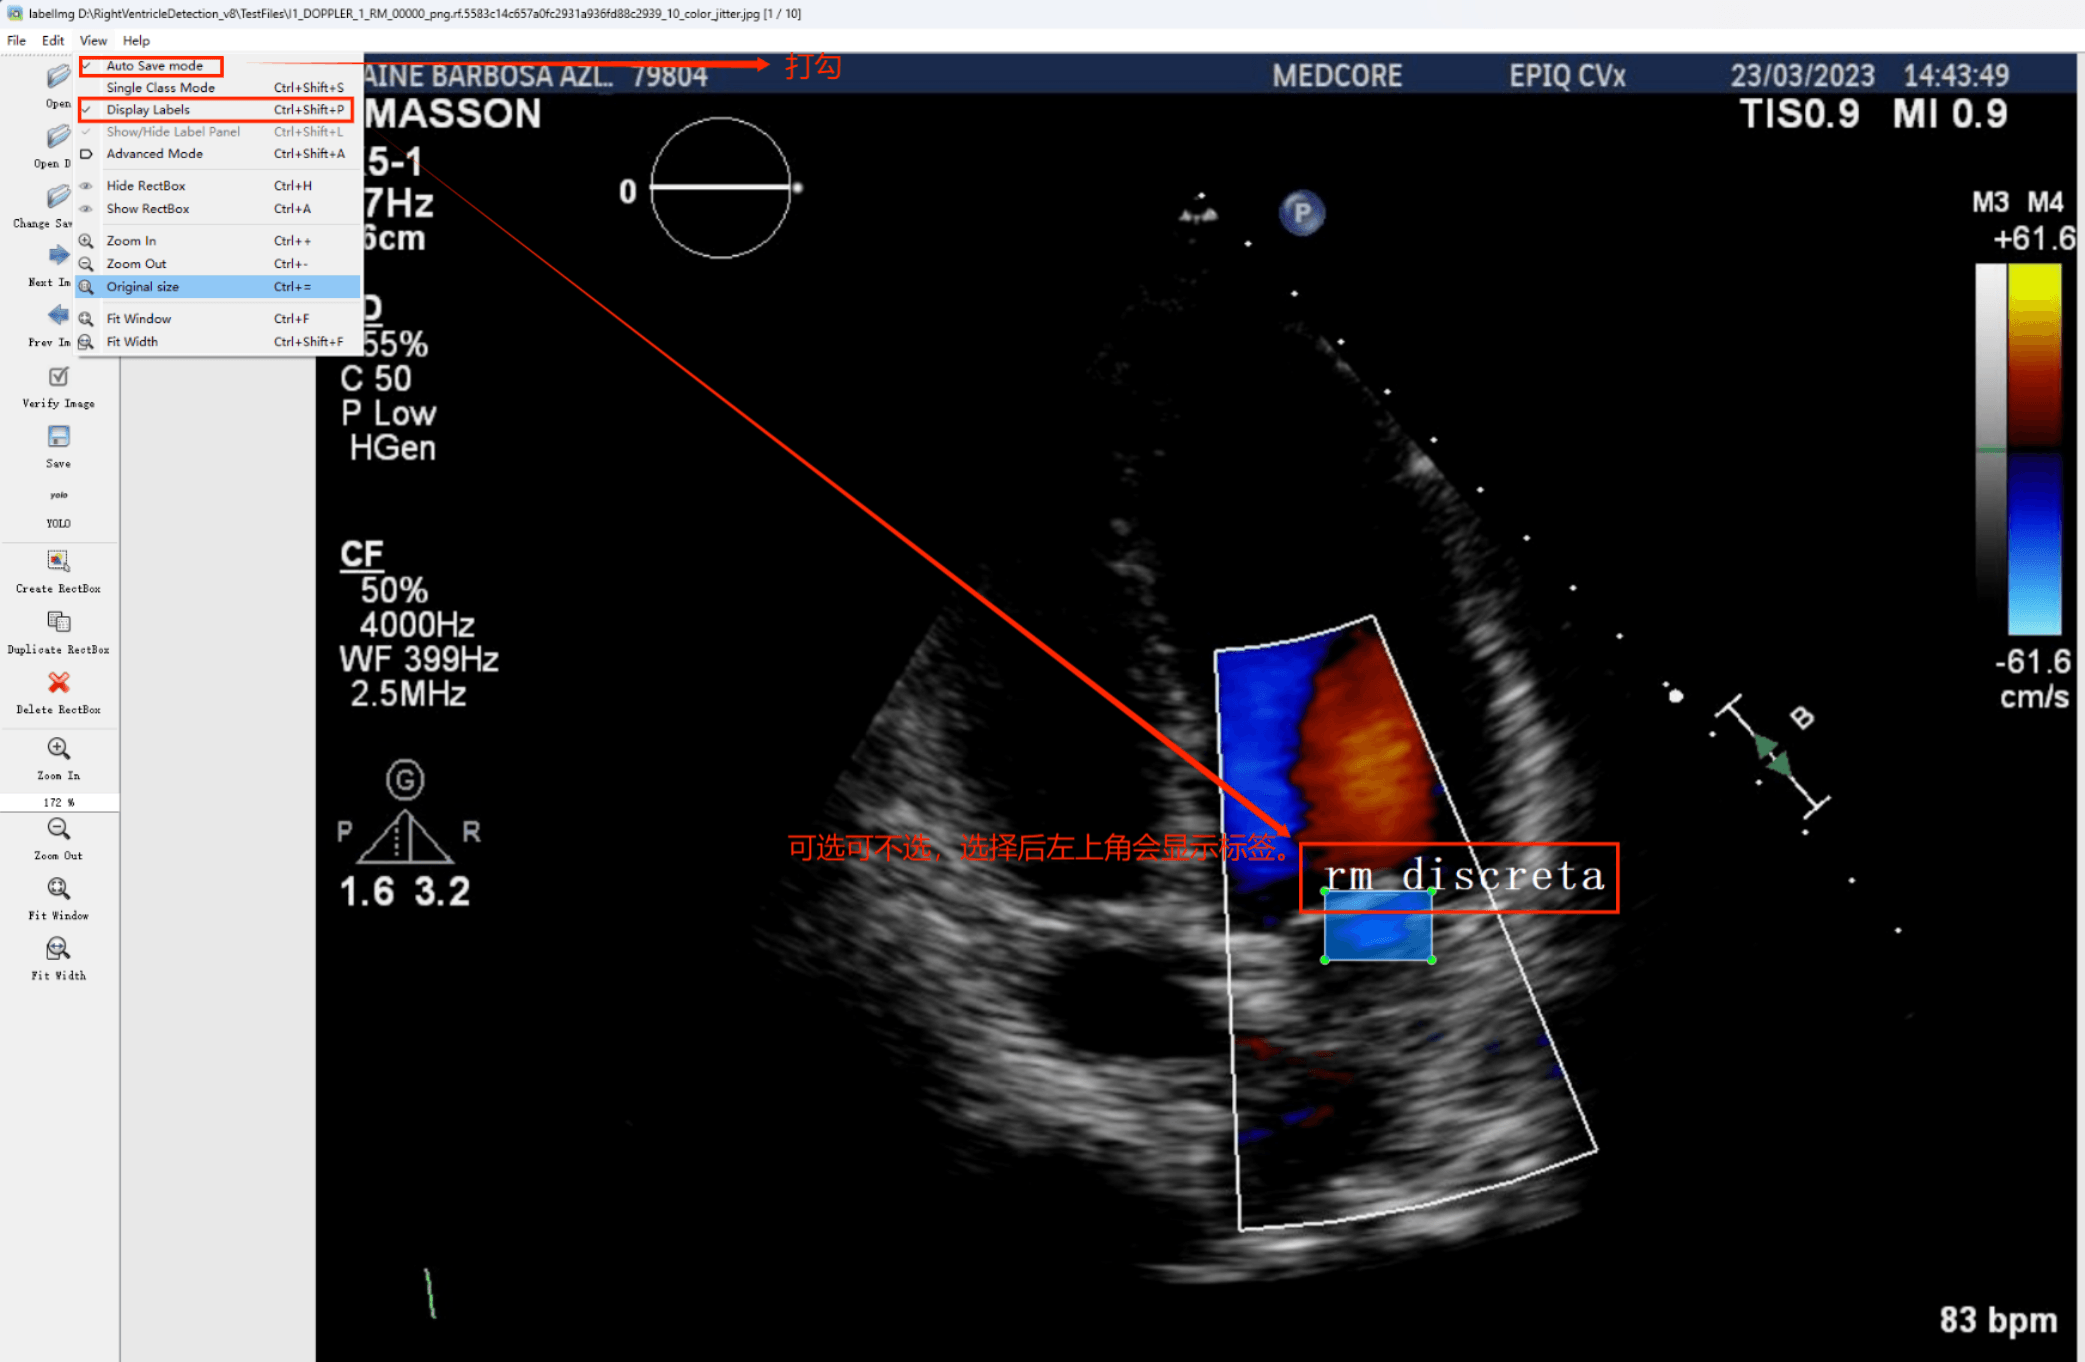

(1)labelimg:开源的图像标注工具,标签可用于分类和目标检测,它是用python写的,并使用Qt作为其图形界面,简单好用(虽然是英文版的)。其注释以 PASCAL VOC格式保存为XML文件,这是ImageNet使用的格式。此外,它还支持 COCO数据集格式。

初识labelimg

打开后,我们自己设置一下

在View中勾选Auto Save mode

接下来我们打开需要标注的图片文件夹

并设置标注文件保存的目录(上图中的Change Save Dir)

接下来就开始标注,画框,标记目标的label,然后d切换到下一张继续标注,不断重复重复。

Labelimg的快捷键